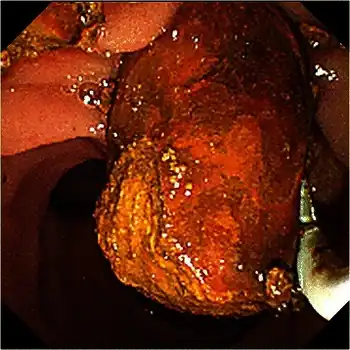

Abdominal ultrasonography of a common bile duct stone -

Treatment is removal of the gallstone from the bile duct using ERCP or an intraoperative cholangiogram. In these procedures, a thin tube is introduced into the common bile duct to perform a cholangiogram. If stones are identified, the surgeon inserts a tube with an inflatable balloon to widen the duct, and the stones are usually removed using either a balloon or tiny basket. A laser can be used to split big stones and make it easier to solve it using laparoscopy.[3]